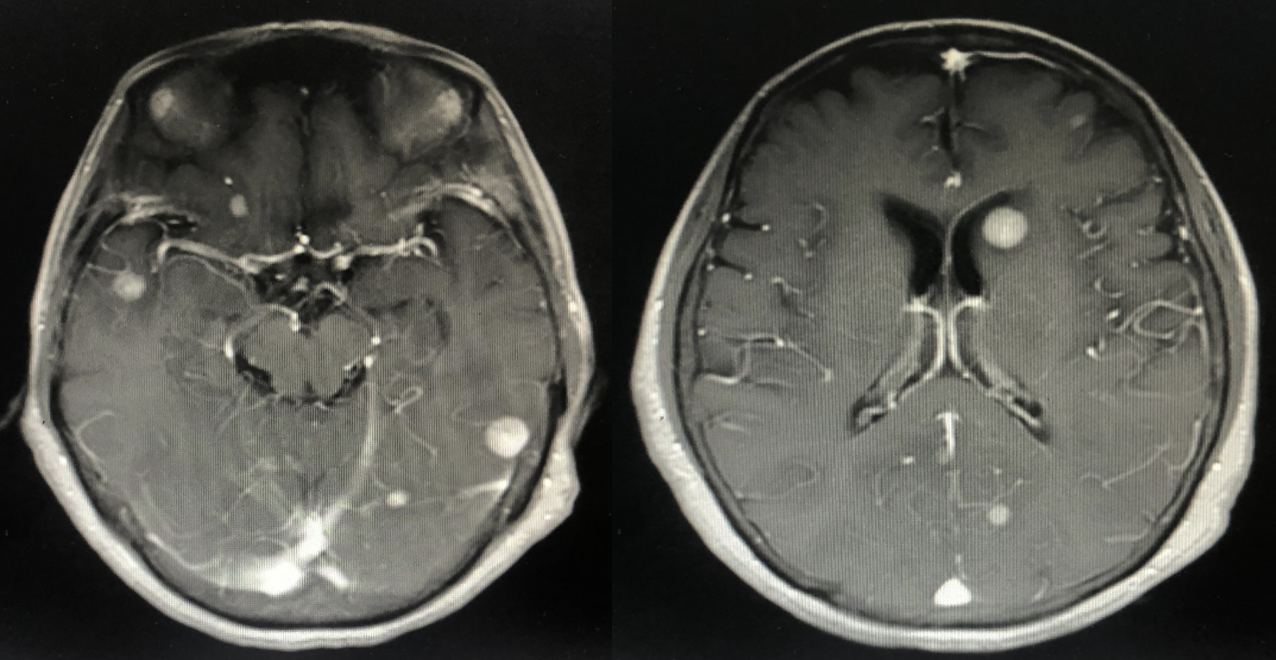

2022年10月头颅MR:脑内多发异常强化灶,结合病史考虑转移。(新发脑转移)

2023年9月头颅增强MR:脑内多发异常强化灶,部分较前缩小。

2024年5月头颅增强MR:脑内多发异常强化灶,较前增多增大。

2024年8月头颅增强MR:脑内多发异常强化灶,较前增多增大,进展。